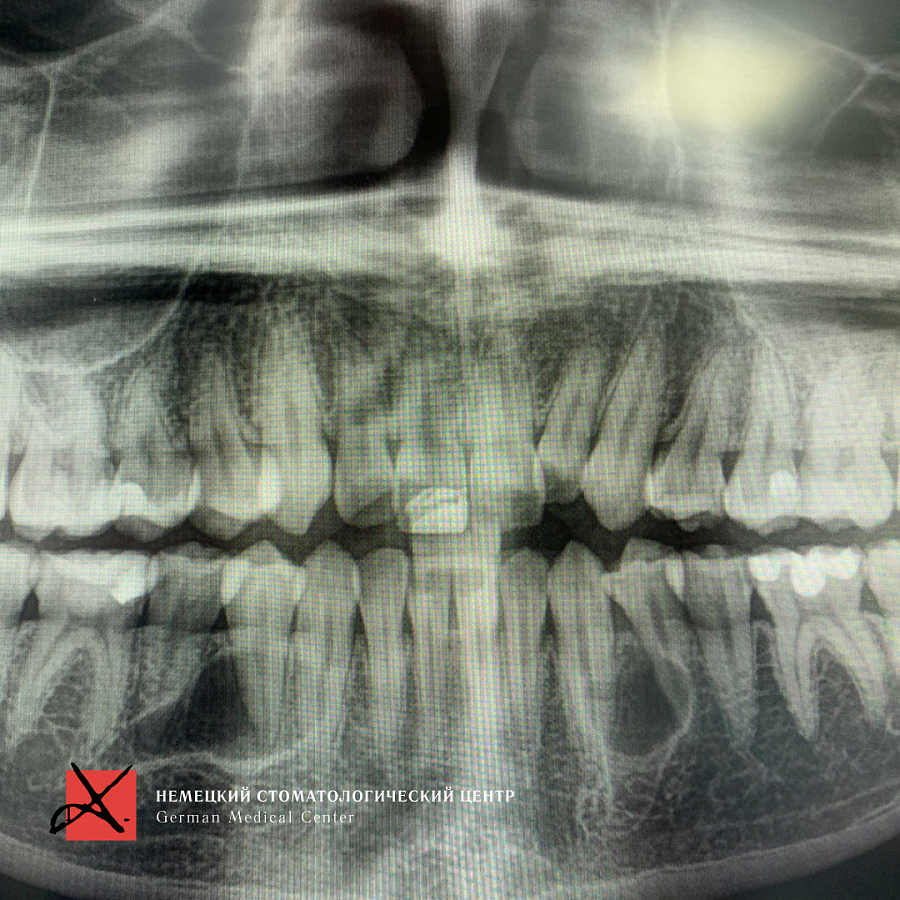

Зубы были удалены через окошко в кости, сделанное изнутри полости рта со стороны языка. Заживление прошло отлично, пациент ни на что не жалуется, соседние зубы не были повреждены.

На данный момент пациент продолжает ортодонтическое лечение.